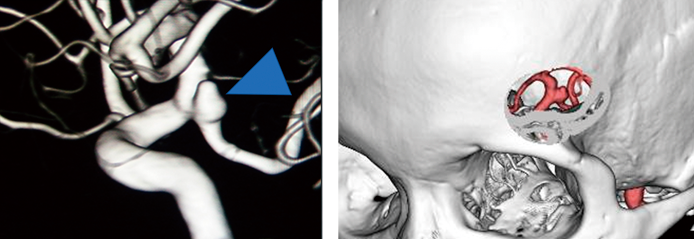

手術にあたっては、まず3D-CTA(3次元CT血管造影)などの最新画像技術を用いて、動脈瘤の形状や周囲の血管との位置関係を立体的に把握します。

その情報をもとに、患者さんごとに開頭部位を緻密にシミュレーションし、最小限の切開で最大限の効果を得られるよう精緻に手術を設定します。患者さんそれぞれに最適な手術戦略を採りますから、テーラーメイド鍵穴手術と呼ぶこともあります。

●鍵穴手術による未破裂動脈瘤のクリッピング術 / CTアンギオグラフィーや3D-CTA(3次元CT血管造影)などを用いて動脈瘤の位置や形状を把握し、それをもとに患者さんそれぞれに最適かつ最小の切開で手術が可能になるよう、シミュレーションを行い、顕微鏡下でクリッピング手術を行います。(青い矢印の部分が動脈瘤)